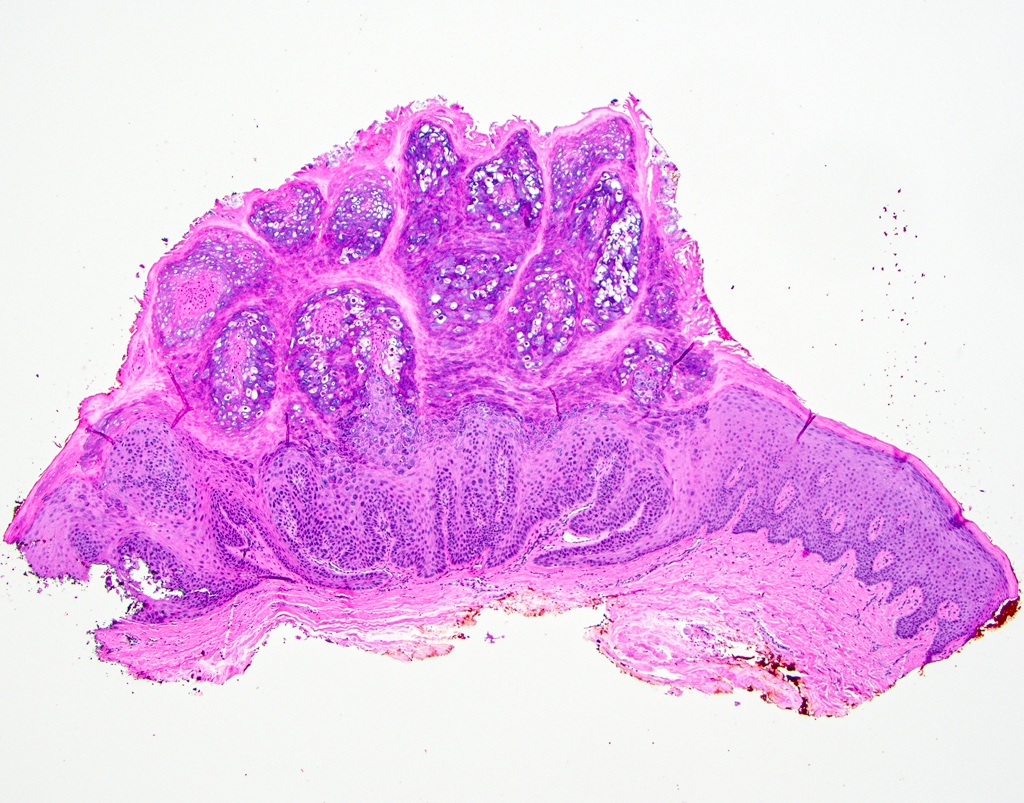

Microscopic (histologic) description

- Similar to cutaneous counterpart (Head Neck Pathol 2019;13:80)

- Prominent surface keratinization (often orthokeratin with superficial parakeratin tufts)

- Inward cupping of the rete pegs

- Exophytic / papillary fronds which form church spire-like peaks

- Hypergranulosis with coarse keratohyalin granules and potential eosinophilic intranuclear viral inclusions within the granular cell layer

- Koilocytosis within the superficial epithelial layers

Microscopic (histologic) images

C. Verruca vulgaris. The microscopic images show a well circumscribed, papillary epithelial proliferation with inward cupping of the rete ridges, prominent koilocytosis and prominent keratohyaline granules, which are all features of verruca vulgaris. Answers A and B are incorrect because condyloma acuminatum and squamous papilloma both lack prominent hypergranulosis while condyloma acuminatum exhibits broad, blunted papillary projections rather than the thin, hyperkeratotic projections seen above. Answer D is incorrect because verrucous carcinoma demonstrates broad, pushing rete ridges and lacks circumscription.

A patient presents with a white lesion on the hard palate. Microscopic examination shows a well defined proliferation of stratified squamous epithelium forming exophytic papillary fronds. The epithelium is covered by a thickened layer of dense orthokeratin, which forms church spires and hypergranulosis and koilocytosis are appreciated. The rete ridges demonstrate prominent inward cupping. What is the diagnosis?

C. Verruca vulgaris. Verruca vulgaris is characterized by a papillary epithelial proliferation with hypergranulosis, inward cupping of the rete ridges and koilocytosis, as described in the question. Answer A is incorrect because condyloma acuminata are not bright white clinically and lack prominent hypergranulosis. Answer B is incorrect because proliferative verrucous leukoplakia may look very similar to verruca vulgaris on small biopsies but proliferative verrucous leukoplakia is not well circumscribed clinically and not isolated. Additionally, proliferative verrucous leukoplakia does not show circumscription and inward cupping of the rete ridges histopathologically. Answer D is incorrect because verrucous carcinoma is traditionally larger clinically and demonstrates a pushing pattern of invasion without circumscription.